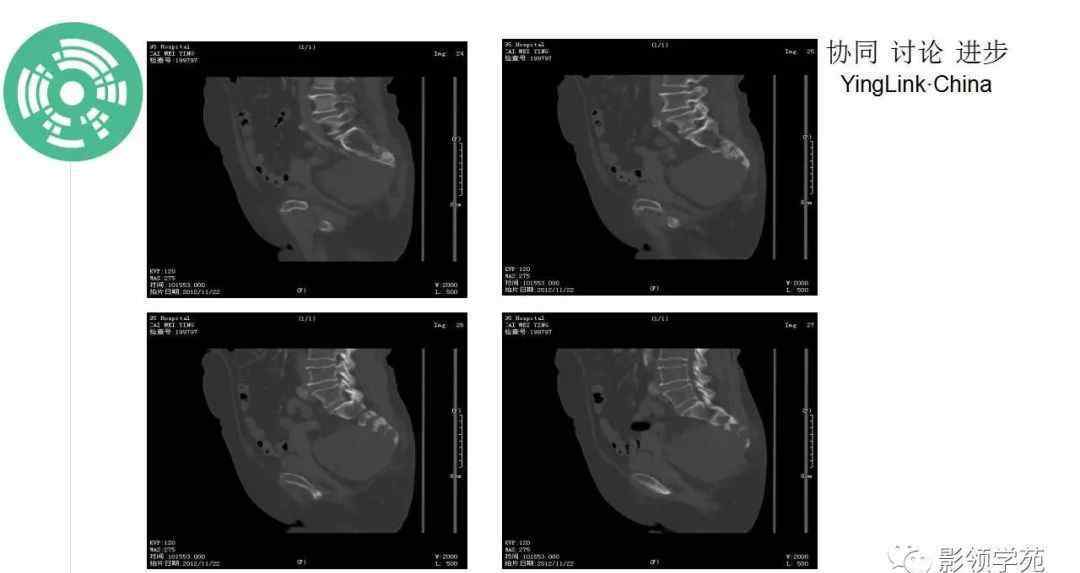

CT:一般表现为溶骨性膨胀性骨质破坏,常伴有软组织肿块,穿插斑片状钙化(钙化率低于软骨肉瘤),少数边缘表现为骨质硬化。